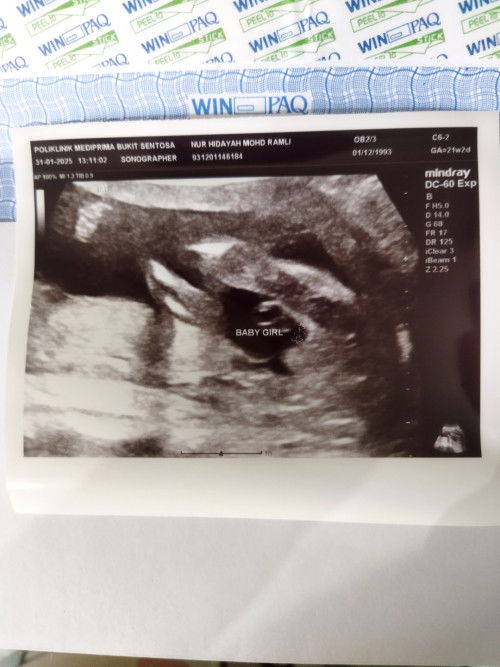

Hai, nk tnya kalo mcm nie agak2 confirm baby girl ke? Tringin nk baby girl...

Scan gender baby girl.